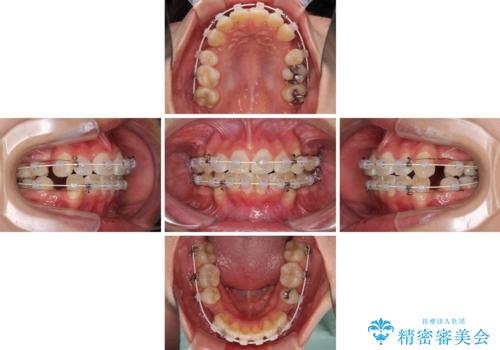

- 審美装置

- 2年3ヶ月

叢生解消のため、上下左右第一小臼歯4本を抜歯し、ワイヤー装置にて矯正治療を行うこととしました。

半年ほどで前歯のデコボコは改善され、汚れの溜まりやすさは解消されました。

抜歯スペースを閉じるために期間がかかりましたが、当初予定通り2年強で終えることができました。